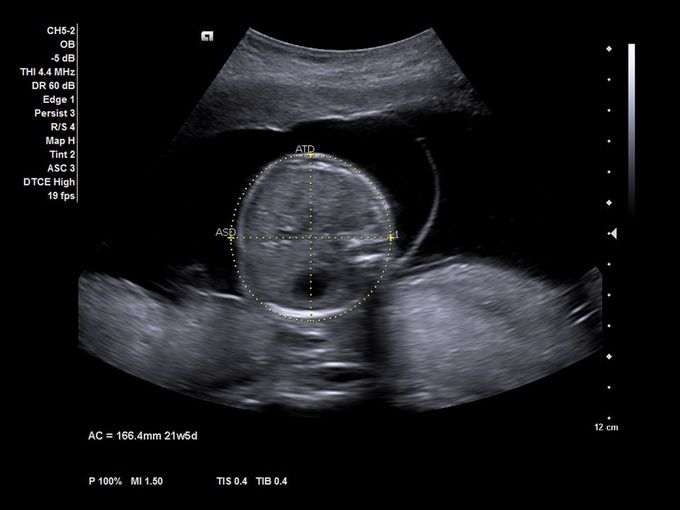

Кроме новой техники, можно заказать восстановленные медицинские системы: ультразвуковые сканеры, томографы, флюороскопы, ангиографы и хирургические установки С-дуга.